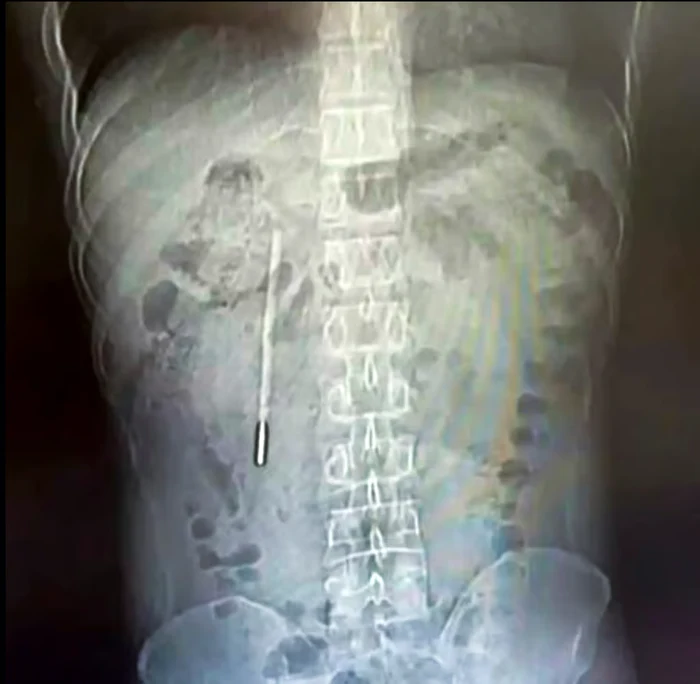

Wang, un bărbat în vârstă de 32 de ani din China se confruntă cu dureri abdominale persistente, așa că a mers la un consult medical. Totul s-a petrecut în orașul Wenzhou din provincia Zhejiang, în sud-estul Chinei. Iar potrivit adevarul.ro, o scanare efectuată de medici a arătat că bărbatul avea un corp străin în duoden.

Specialiștii și-au dat seama imediat că poate fi vorba despre un termometru cu mercur, iar vârful acestuia apăsa deja direct pe peretele intestinal și exista riscul apariției unei hemoragii interne severe.

Din fericire, medicii chinezi au reușit să înlăture termometrul fără probleme. Întreaga procedură a durat undeva în jur de 20 de minute, însă a fost una foarte delicată. Obiectul se afla foarte aproape de căile biliare și exista riscul de lezare a peretelui intestinal.